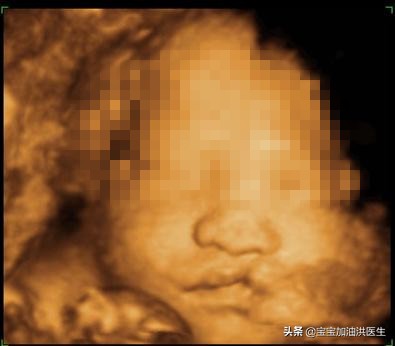

产前超声检查中发现了胎儿一边的唇部是裂开的